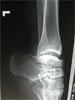

Pre

Op

Old polio leg in 38year old male with 5cm shortening lower leg and equinus foot(partially correctible).Previous triple arthodesis done elsewhere many years ago